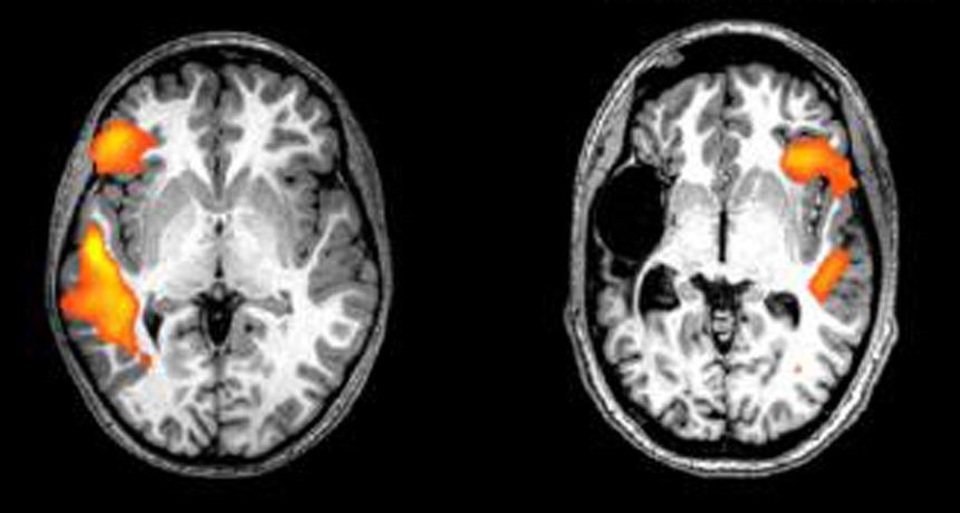

Phim chụp cộng hưởng từ (MRI) của anh chị em ruột khỏe mạnh của các bệnh nhân đột quỵ cho thấy hoạt động của trung khu ngôn ngữ nằm ở bán cầu não trái khi đối tượng nghiên cứu lắng nghe thông tin. Bệnh nhân đột quỵ cho thấy có hoạt động ở những khu vực tương tự - chỉ là ở bên đối diện của não.